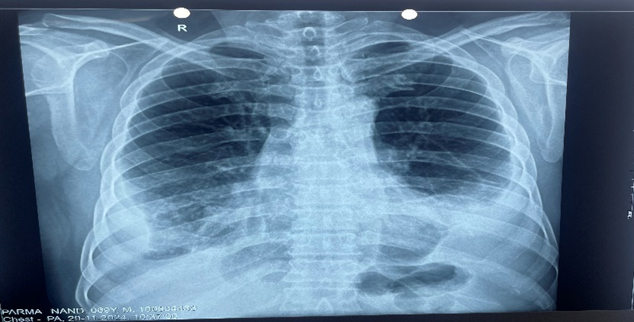

A 69-year-old male came to our emergency with complaints of breathlessness for 3 months which was insidious onset and progressive. He had chest tightness, and cough with whitish mucoid sputum for 1 month. He initially had chest pain 3 months back but it decreased gradually. There was no history of fever, He had a history of pulmonary tuberculosis 40 years back for which he took 9 months of antitubercular therapy. He was a smoker but did not consume alcohol. He was hypertensive for 10 years and was nondiabetic. There was no history of trauma, surgery, or any other interventions in the past. On admission, his blood pressure was 134/90 mm Hg, pulse 102/min, oxygen saturation 88% on room air, and respiratory rate 32/min. There was no pallor, icterus, cyanosis, clubbing, pedal edema, or lymphadenopathy. On inspection, there were decreased chest movements in infra-axillary and mammary areas. On percussion stony dull sound was noticed in the infrascapular, and infra-axillay regions bilaterally. On auscultation, there were decreased air entry in the infrascapular regions bilaterally and S3 gallop prominent Electrocardiogram (ECG) was suggestive of right bundle branch block pattern. Trop T was negative. Chest radio-graph showed blunting of bilateral costophrenic angles. Blood investigations were as follows: hemoglobin 13.2 gm/dl, leucocytes 8110/mm3, platelets 4.24 lakh/mm3, blood urea 31.4 mg/dl, creatinine 0.91 mg/dl, bilirubin 0.5 mg/dl, AST 43 IU/L, ALT 56 IU/L, total protein 5.6 gm/dl4, LDL 98 mg/dl, HDL 29 mg/dl, Triglyceride 125 mg/dl, VLDL 25 mg/dl, blood glucose 138 mg/dl. The urine examination was within normal limits. The patient's abdominal ultrasound was normal. Patients' viral markers HIV, HBsAg, and HCV was negative. Sputum Ziehl neelsen stain and gene xpert were negative for tuberculosis. Thoracic ultrasound revealed bilateral pleural effusion. Under ultrasound guidance, thoracocentesis was done. Pleural fluid was milky in color and its biochemical pathological and microbiological reports were as follows pleural fluid protein 4.06 gm/dl, glucose 137mg/dl, ADA 12.6 IU/L, LDH 806 mg/dl, triglyceride 381 mg/dl, cholesterol 51 mg/dl, gene xpert of pleural fluid was negative for mycobacterium tuberculosis. The culture was sterile. The total leucocyte count was 1000 of which 95%were lymphocytes and 5% neutrophils cytology was negative for malignant cells and no fungal element was seen. Thus, a diagnosis of chylothorax was made. Contrast-enhanced computer tomography was suggestive of a patchy area of consolidation/collapse with few specs of calcifications within and adjacent thin atelectatic bands seen in basal segments of bilateral lower lobes. There was no mediastinal lymphadenopathy. Bilateral pleural effusion seen with underlying atelectatic changes. 2D Electrocardiography revealed dilated cardiac chambers, severe left ventricles dysfunction with ejection fraction of 25-30%. Thus, after ruling out other possible causes of chylothorax, we made a diagnosis of chylothorax due to congestive heart failure which is a rare entity. After starting the treatment for congestive heart failure, patient showed significant improvement symptomatically and Chest radiograph also showed decreased amount of pleural effusion. He was discharged on stable vitals with oxygen saturation 95% on room air.

Figure 2: Chest x-ray.